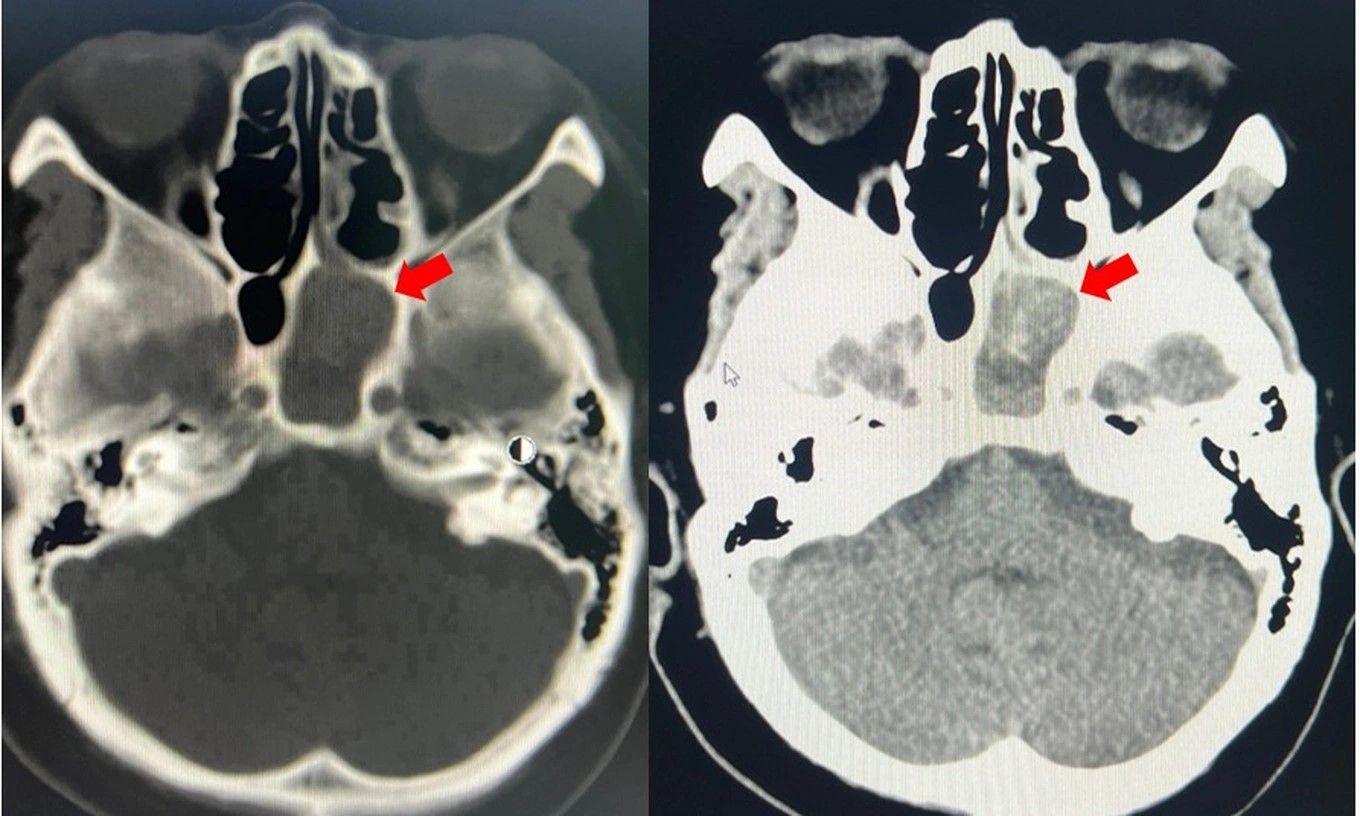

Kết quả chụp CT scan và cận lâm sàng sau đó cũng xác định người bệnh mắc viêm xoang bướm trái do nấm kèm tình trạng nhiễm trùng. Bên cạnh đó, bà cũng được ghi nhận mắc nhiều bệnh nền như tăng huyết áp, bệnh thận mạn giai đoạn III, đái tháo đường type 2.

| Hình ảnh khối nấm xoang bướm bên trái (mũi tên đỏ) (Ảnh: BV). |